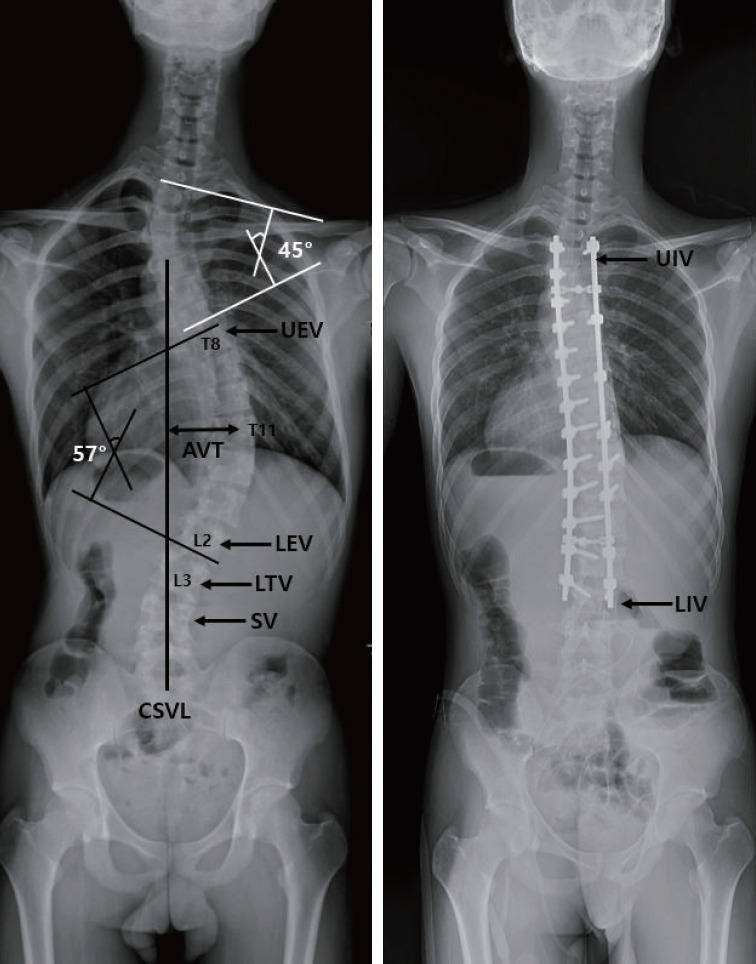

Adolescent idiopathic scoliosis (AIS), which is associated with an extensive range of clinical and radiological presentations, is the one of the most challenging spinal disorders. The goals of surgery are to correct the deformity in 3 dimensions and to preserve motion segments while avoiding complications. Despite the ongoing evolution of classification systems and algorithms for the surgical treatment of AIS, there has been considerable debate regarding the selection of an appropriate fusion level in AIS. In addition, there is no consensus regarding the exact description, relationship, and risk factors of coronal decompensation following selective fusion. In this review, we summarize the current concepts of selection of the fusion level for AIS and review the available information about postoperative coronal decompensation.

青少年特发性脊柱侧凸(AIS)与广泛的临床和放射学表现相关,是最具挑战性的脊柱疾病之一。手术的目标是在三维空间上矫正畸形,并保留活动节段同时避免并发症。尽管用于AIS手术治疗的分类系统和算法不断发展,但关于AIS中合适融合节段的选择仍存在相当大的争议。此外,对于选择性融合后冠状面失代偿的确切描述、关系及危险因素尚无共识。在本综述中,我们总结了目前关于AIS融合节段选择的概念,并回顾了有关术后冠状面失代偿的现有信息。